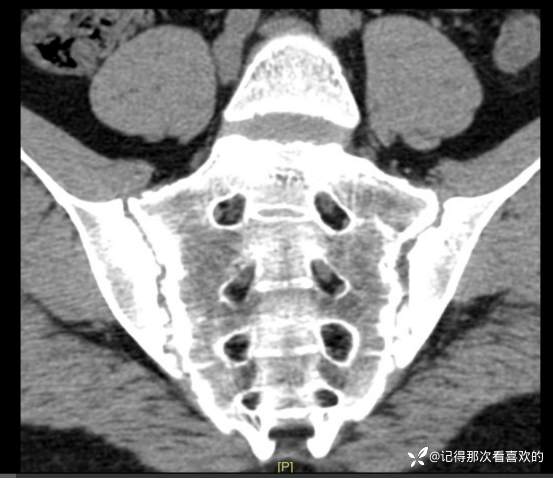

06-04 胸部CT平扫|骶髂部CT平扫:1、双肺下叶少许慢性炎及纤维灶,部分呈间质性改变可能。2、左肺下叶小结节,随诊。3、扫及脂肪肝。4、扫入胸椎椎体毛糙略呈竹节样改变,请结合临床。5、骶髂关节异常改变,考虑骶髂关节炎,强直性脊柱炎可能?请结合临床及相关检查,随诊。

06-05 骶髂关节MRI平扫:1、双侧骶髂关节改变,符合为强直性脊柱炎所致。请结合临床实验室检查结果。2、左髋关节少量积液。请结合临床及其他检查,随诊。